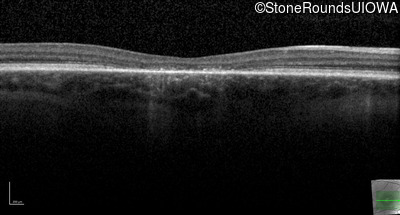

Optical Coherence Tomography - Right - 10/100 -1

Exemplar / OCT Stack

Optical Coherence Tomography - Left - 10/100 -2